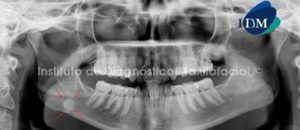

Paciente de sexo femenino y de 59 años de edad es referida al Instituto de Diagnóstico Maxilofacial para realizar el estudio de evaluación ósea para la colocación de implantes, lo cual llamo nuestra atención la presencia de un hallazgo radiográfico en el maxilar inferior.